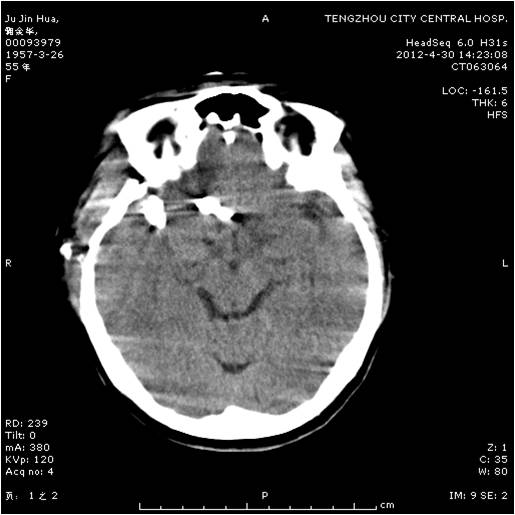

动脉瘤夹闭术前 动脉瘤夹闭术后